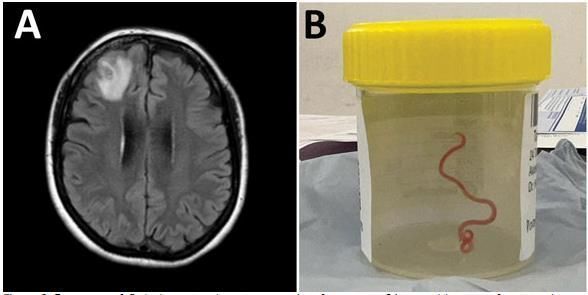

이 여성의 뇌에는 비단뱀에서 볼 수 있는 회충의 종류로 '오피다스카리스 로베르시'라는 벌레가 있었으며 문제는 이 회충이 살아서 꿈틀 거렸다고 하였습니다.

이렇게 사람의 몸에서 발견된 것은 처음이며, 회충의 길이는 8Cm정도의 길이로 생각만 해도 끔찍한 모습이 아닐 수 없습니다.